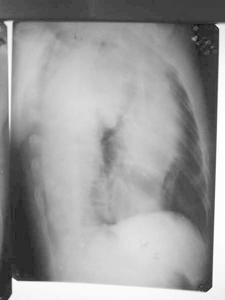

(1)X線計算機斷層掃描(CT)對診斷也有用。胸主動脈瘤的後前位X線片示升主動脈邊緣較膨隆,主動脈增寬,食管主動脈壓跡增寬,降主動脈輪廓顯著不整齊,有多發動脈瘤形成。胸主動脈瘤的左前斜位X線片示主動脈弓部上緣可見波浪狀輪廓,食管隨主動脈迂曲,波浪狀邊緣代表相鄰主動脈的不規則擴張和動脈瘤。(2)MRI檢查在判斷瘤體大小及其與腎動脈和髂動脈的關係上價值等同於CT及腹部超聲。MRI的主要不足是圖象分析費時費用高。